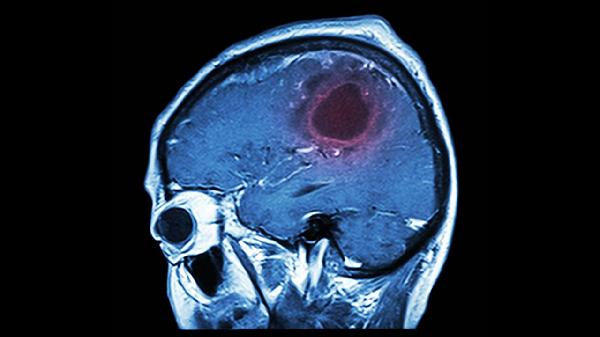

脑溢血发生前会有7个前兆,出现一个以上,及时去检查